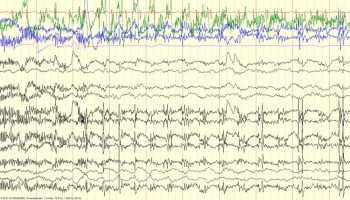

Practice EEG with hundreds of tracings of normal variants, artifacts, and high-yield pathology. Learn how to read EEG and ace your exams!

Developmental/Neonatal Patterns

Neonatal EEG artifacts

Normal Variants